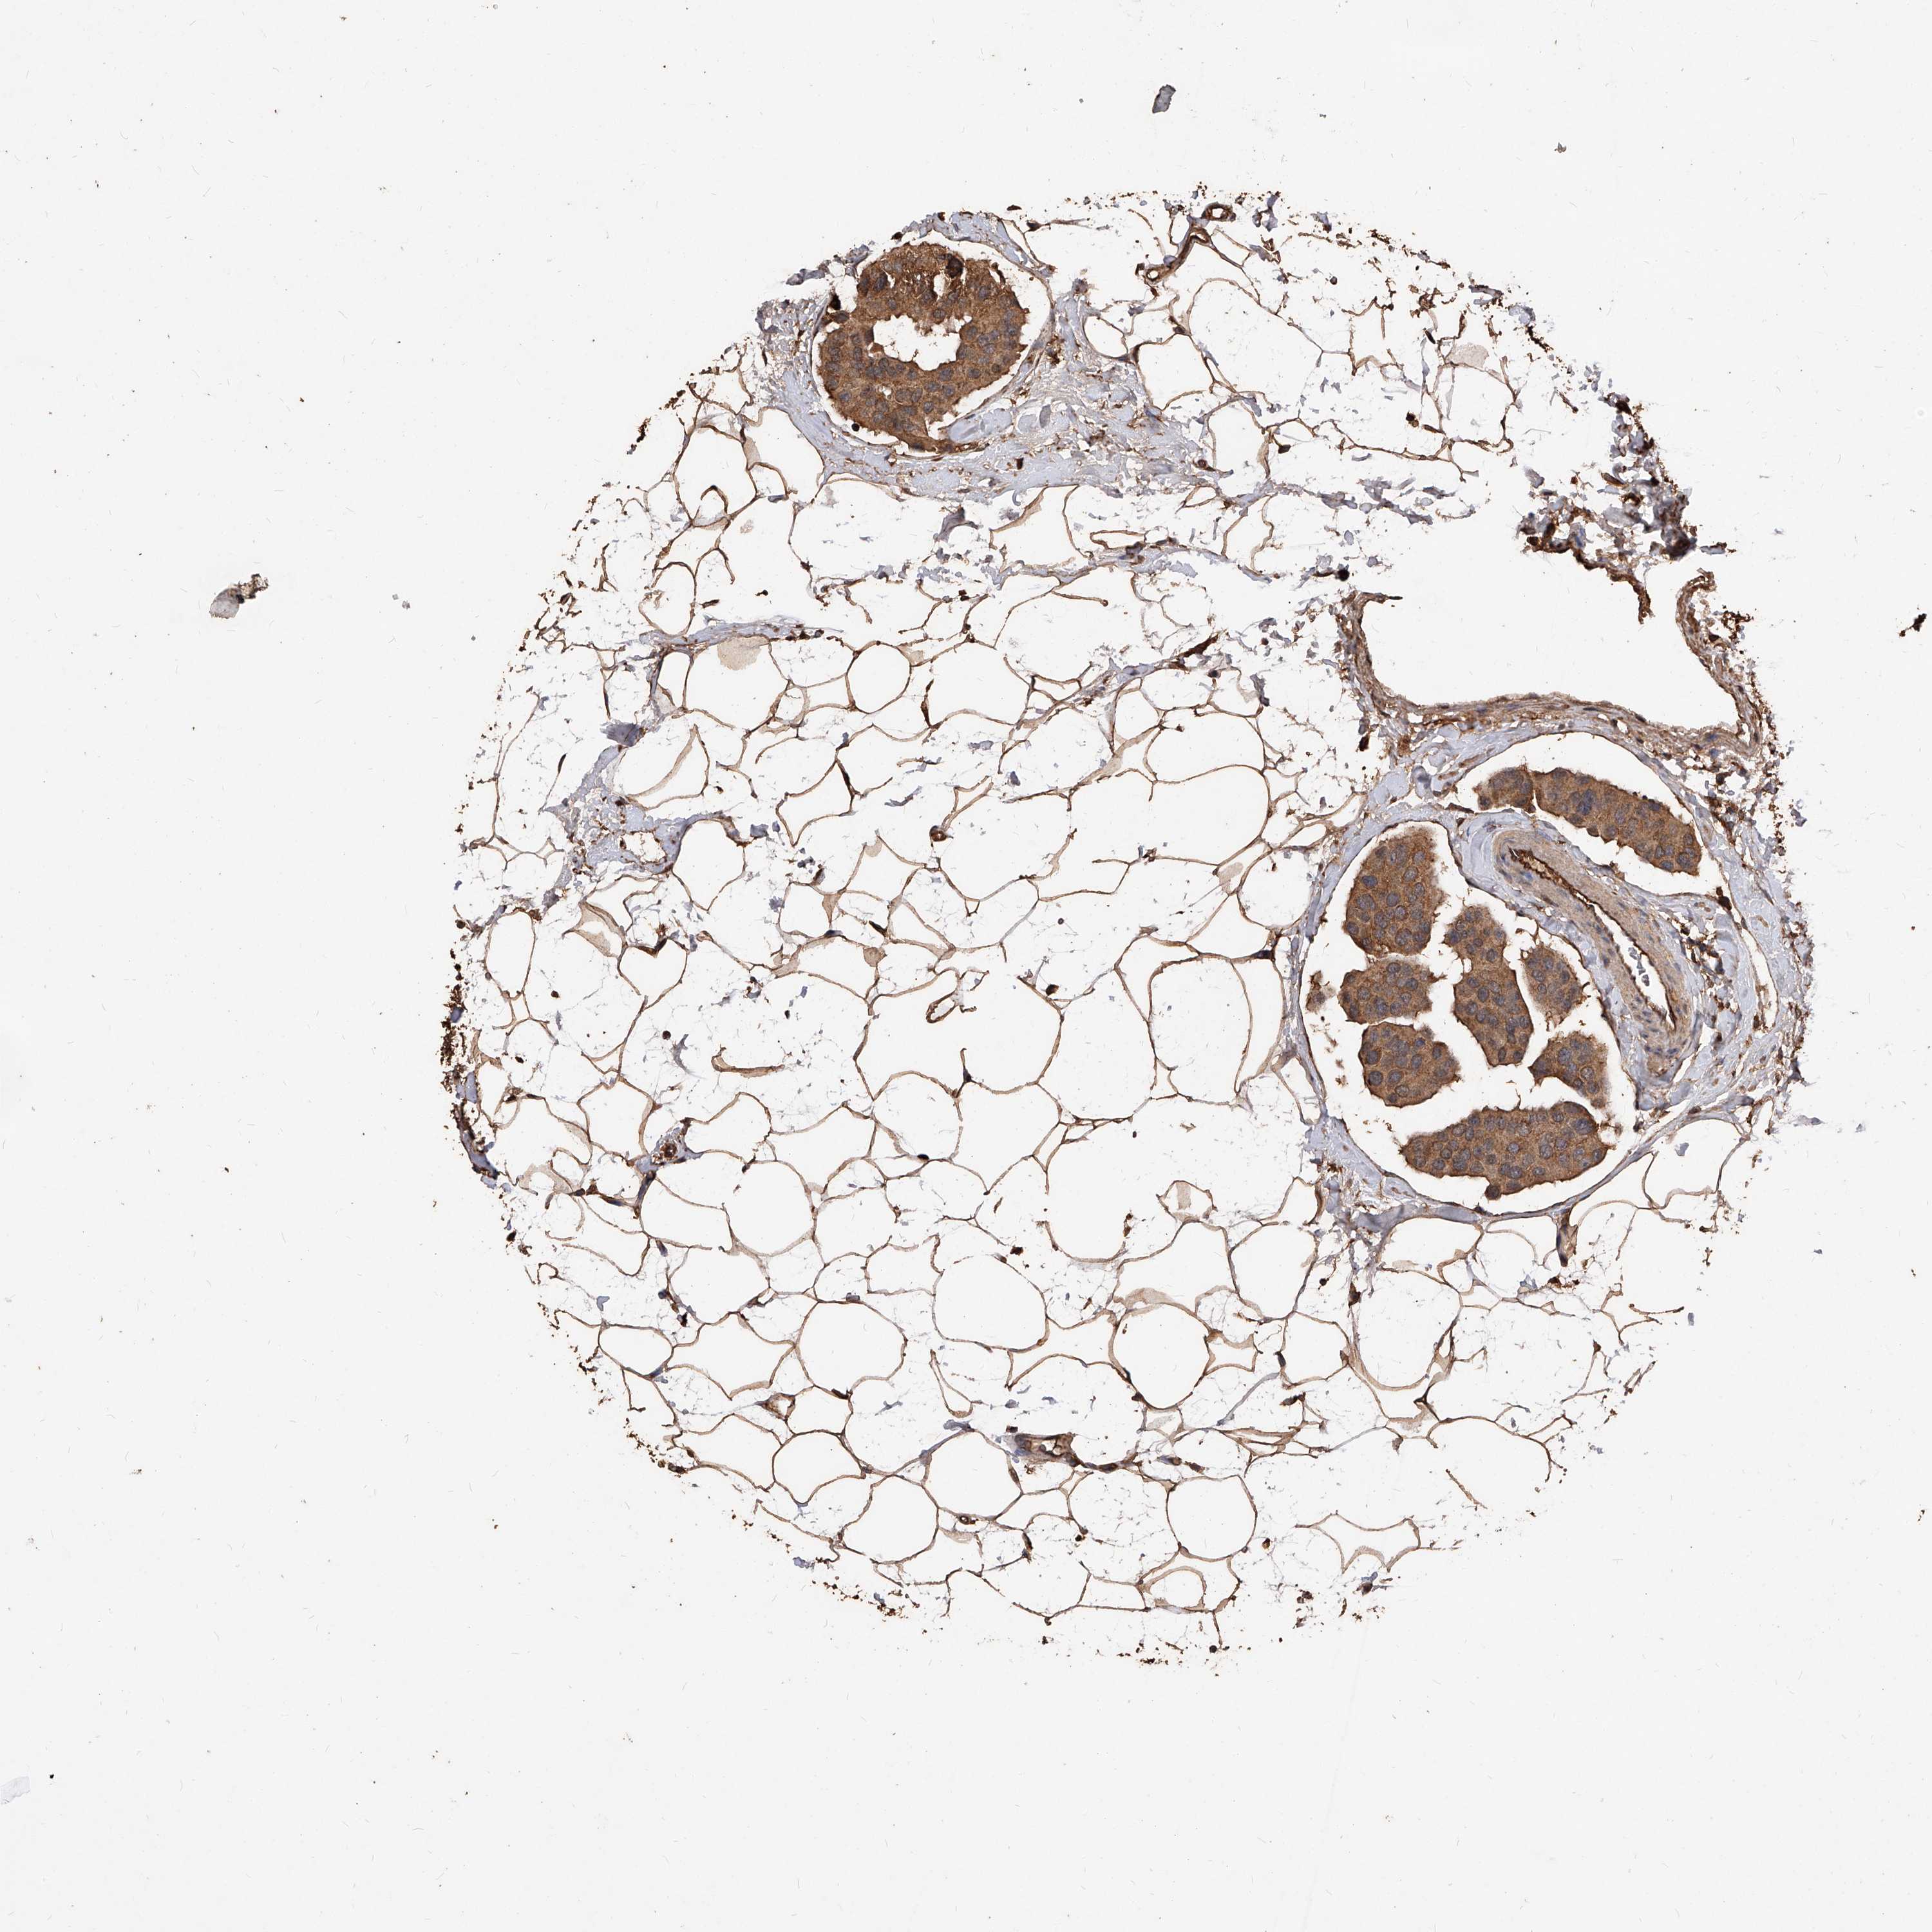

BRCA TCGA BRCA VALIDATION PROTEIN EXPRESSION